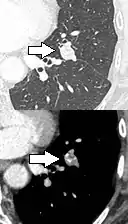

Low attenuating nodule (in this case a fat containing hamartoma).[9]

Cavitation with relatively thick wall, in this case aspergilloma).[9]